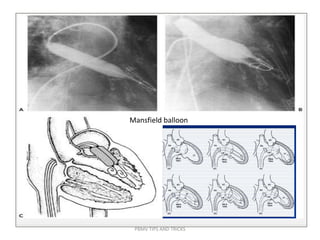

Fully inflated PMV balloon across MV in RAO view. Note the alignment of long axis of

balloon catheter along the long axis of LV cavity

PBMV TIPS AND TRICKS